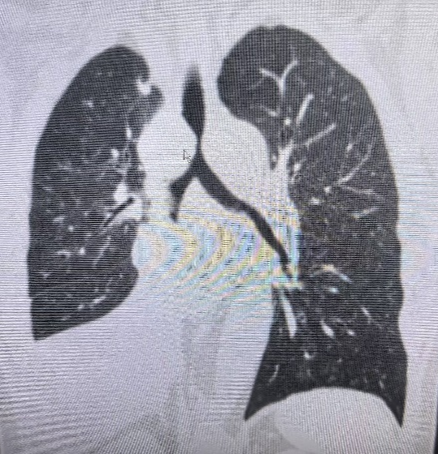

术后一周复查